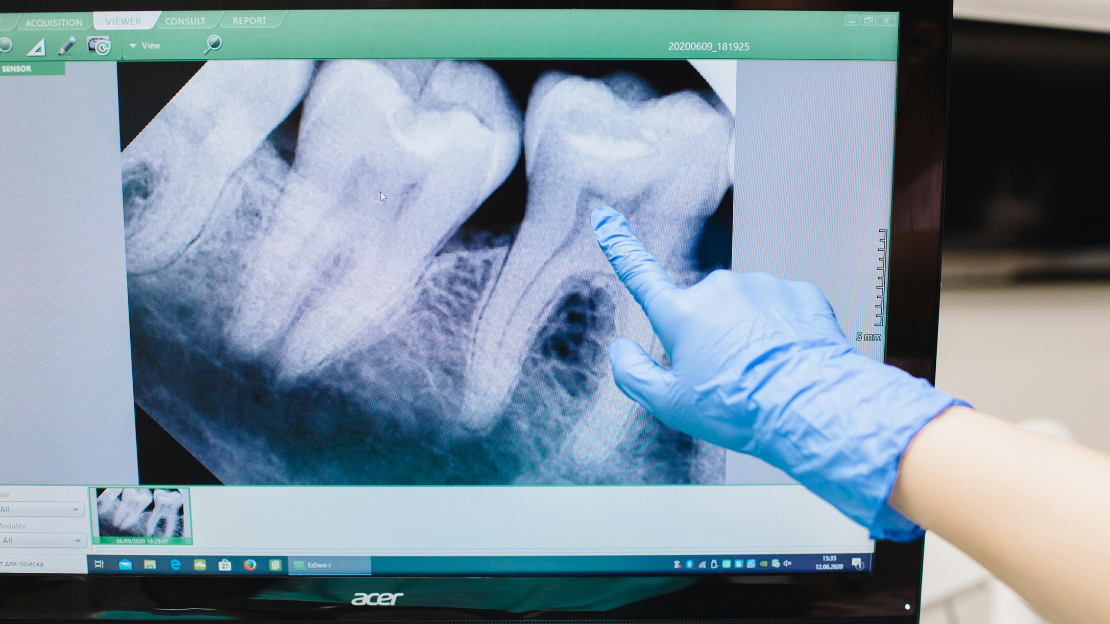

Early evaluation through X-rays helps determine if wisdom teeth surgery is necessary, often preventing more complex issues later in life.

- Schedule a consultation and X-rays for personalized planning.